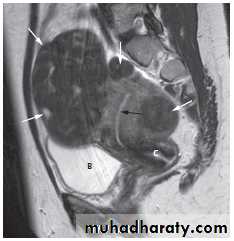

Magnetic resonance imagingPelvic anatomy is very well demonstrated because of the excellent soft tissue contrast afforded by MRI. Images are usually taken in the axial, coronal and sagittal planes . T2-weighted sagittal images show the vagina and cervix in continuity with the body of the uterus.

The zonal anatomy of the uterus is best demonstrated on T2-weighted images, with the endometrium having a high signal intensity, the adjacent inner myometrium (junctional zone) a low signal intensity, and the myometrium an intermediate signal intensity .

At CT fibroids are usually the same density as the adjacent myometrium. MRI can readily identify fibroids as they typically have a different signal characteristic from the normal uterus .

On MRI, there is focal or diffuse thickening of the junctional zone and, in some cases, multiple bright projections are seen extending from the endometrium into the myometrium .